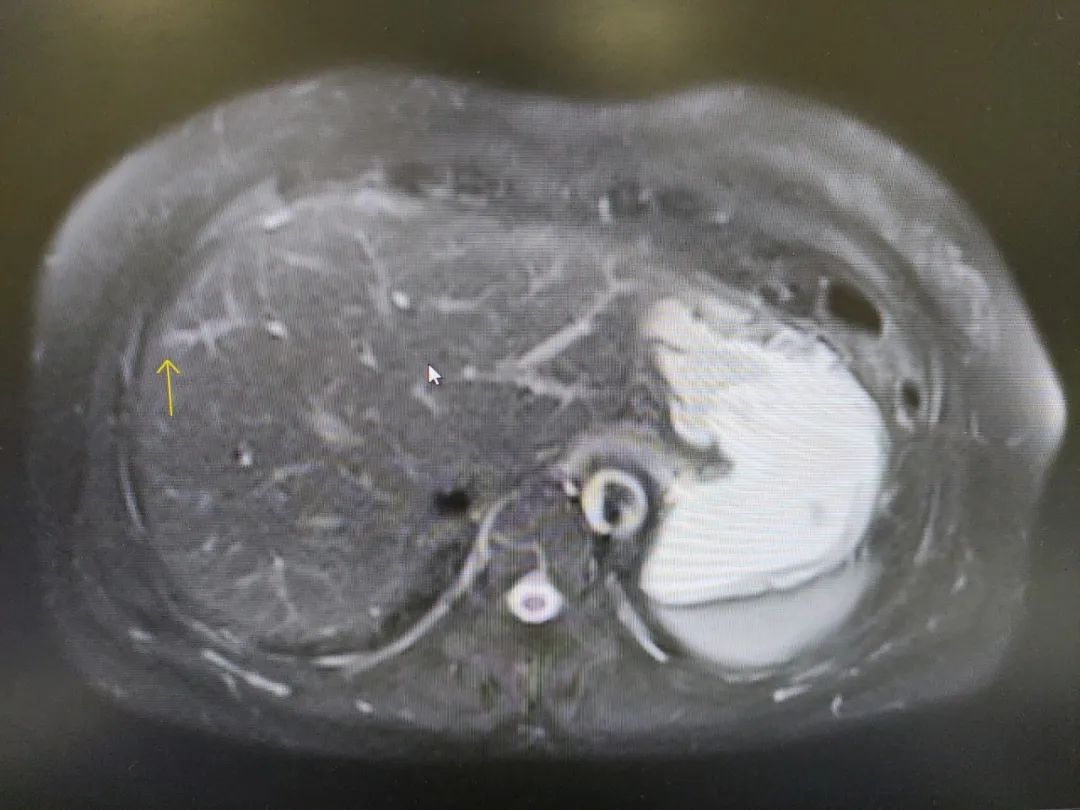

然而在术后定期复检中,腹部增强 MRI 提示赵阿姨肝左外叶结节有增大,这引起了东阳市人民医院肝胆外科副主任医师赵思聪的注意:癌细胞很可能已经转移至肝脏。这也意味着赵阿姨需要进行第二次手术来切除癌变的部分,即腹腔镜手术。

根据检查结果,赵医生发现了两处病灶,但其中有一处并不清晰(见图 2)。于是为赵阿姨联系了上海复旦大学附属中山医院肝胆外科微创专科主任王晓颖教授。